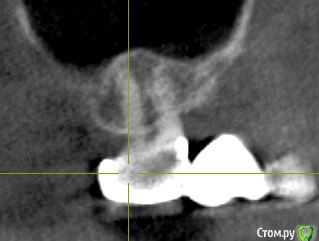

ТСВ Опубликовано 29 июня, 2015 Поделиться Опубликовано 29 июня, 2015 Подскажите пожалуйста!17 зуб, на нем мост. Сделал КТ, там такая картина, прикрепляю несколько срезов.Если это киста, то только удаление вместе с зубом? Ссылка на комментарий

red_butler Опубликовано 29 июня, 2015 Поделиться Опубликовано 29 июня, 2015 Кисты нет, а вот повторное лечение корневых каналов требуется 2 Ссылка на комментарий

Alejandro Опубликовано 30 июня, 2015 Поделиться Опубликовано 30 июня, 2015 Вы имеете в виду очаг просветления в области середины дистального щёчного корня? Ссылка на комментарий